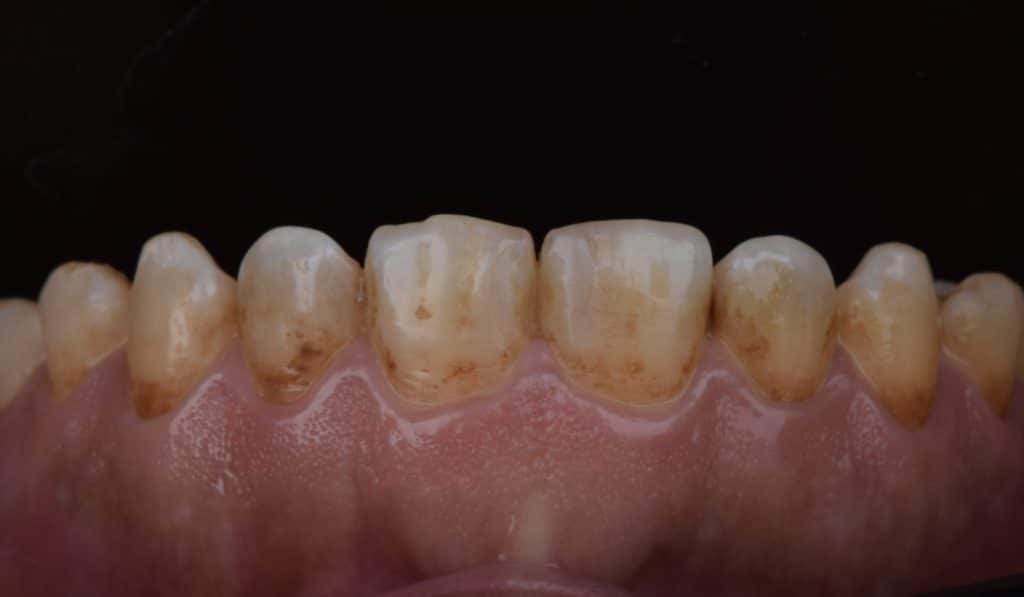

A 36 yrs old female patient presented with class lll incisor relation with anterior open bite (dental component) on skeletal 3 , proclined lower anterior and decreased incisal show ; that was complicated by generalized enamel hypoplasia and multiple caries spots on some of the teeth

1- restore the carious teeth with composite

3- indirect lithium disilicate partial coverage for all the teeth in smile